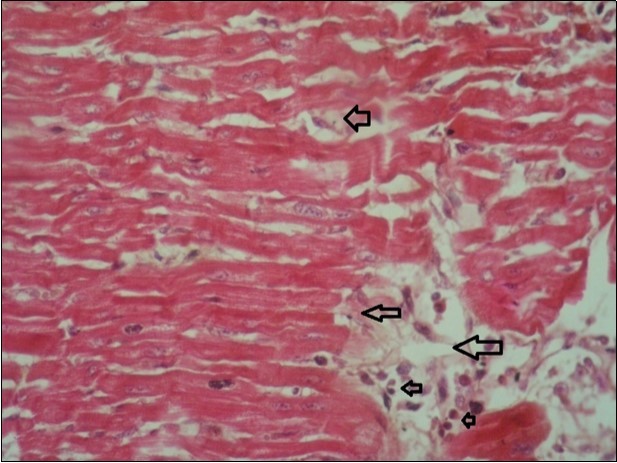

Figure 11.heart (dead cattle less than 1 year old) showed vesicular nuclei of myocytes which suffering hydropic degeneration. Some inflammatory cells (neutrophils, esinophils, lymphocytes) substitute an area of necrosis inside myocardium bundles (arrows). (H &E, X 40)